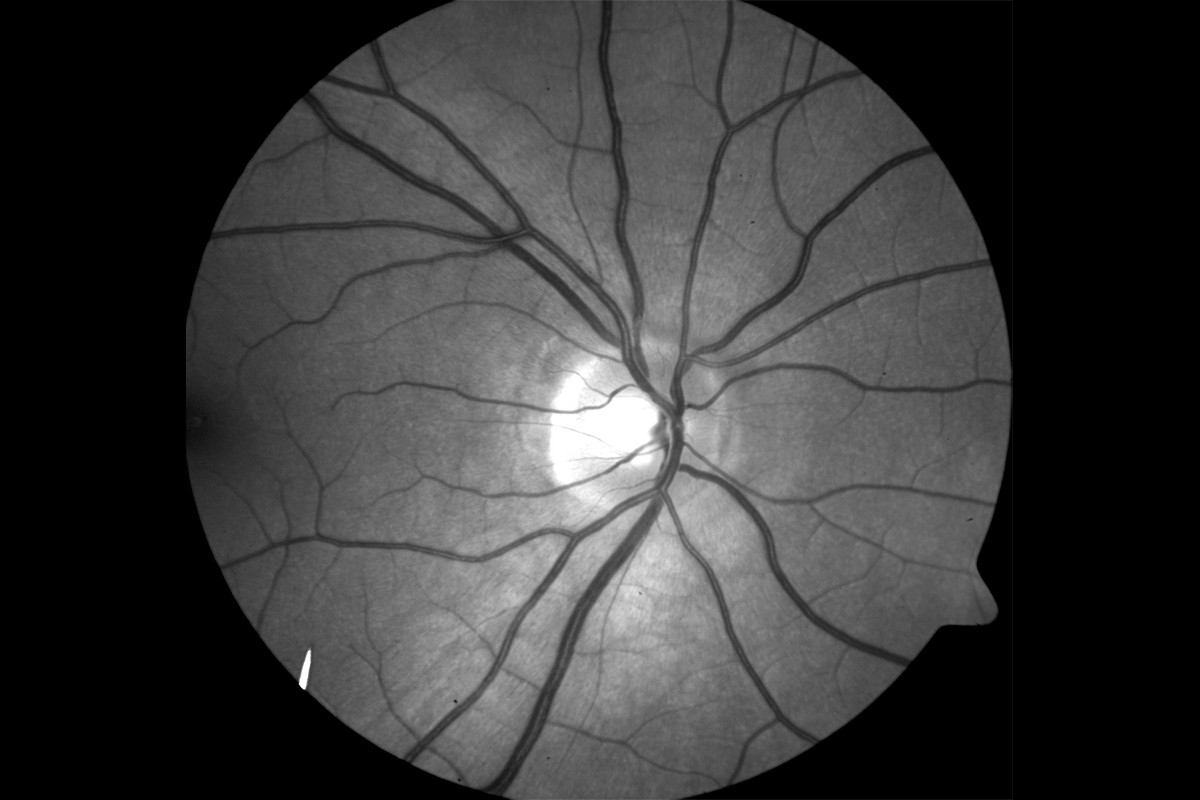

VesselMap aric: Image of the ocular fundus with measuring rangeVesselMap aric: Image of the ocular fundus with measuring range

• VesselMap aric: Image of the ocular fundusVesselMap aric: Image of the ocular fundus

1. Images from the ocular fundus are taken by using an imaging system.

2. The fundus image is opened in the software and the papilla is marked. Therefore, a measurement grid is placed on the image.

3. Subsequently, within this measurement grid (ring zone), all essential arterial and venous vessels are marked manually by selecting and clicking on them.

4. The software now determines the vessel diameters according to the marked vessels and calculates the static vessel parameters.

The recording of the fundus images, determination of the parameters and evaluation of the static vessel parameters are carried out on the basis of the ARIC study.